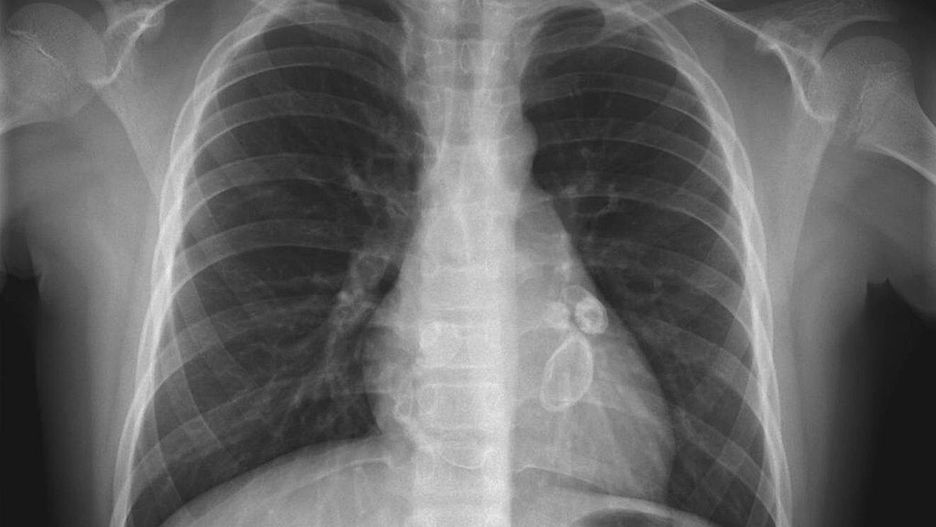

Radiogram klatki piersiowej pacjenta z chorobą Kawasaki. Nowa choroba jest do niej podobna

Źródło zdjęć: © Domena publiczna

Choroba, która przypomina chorobę Kawasaki, określana jest jako "pediatryczny wielosystemowy zespół zapalny". Do objawów zaliczają się zapalenie spojówek, gorączka, wysypka i biegunka. Podejrzewa się, że ma związek z koronawirusem, ale wciąż niewiele o niej wiadomo.